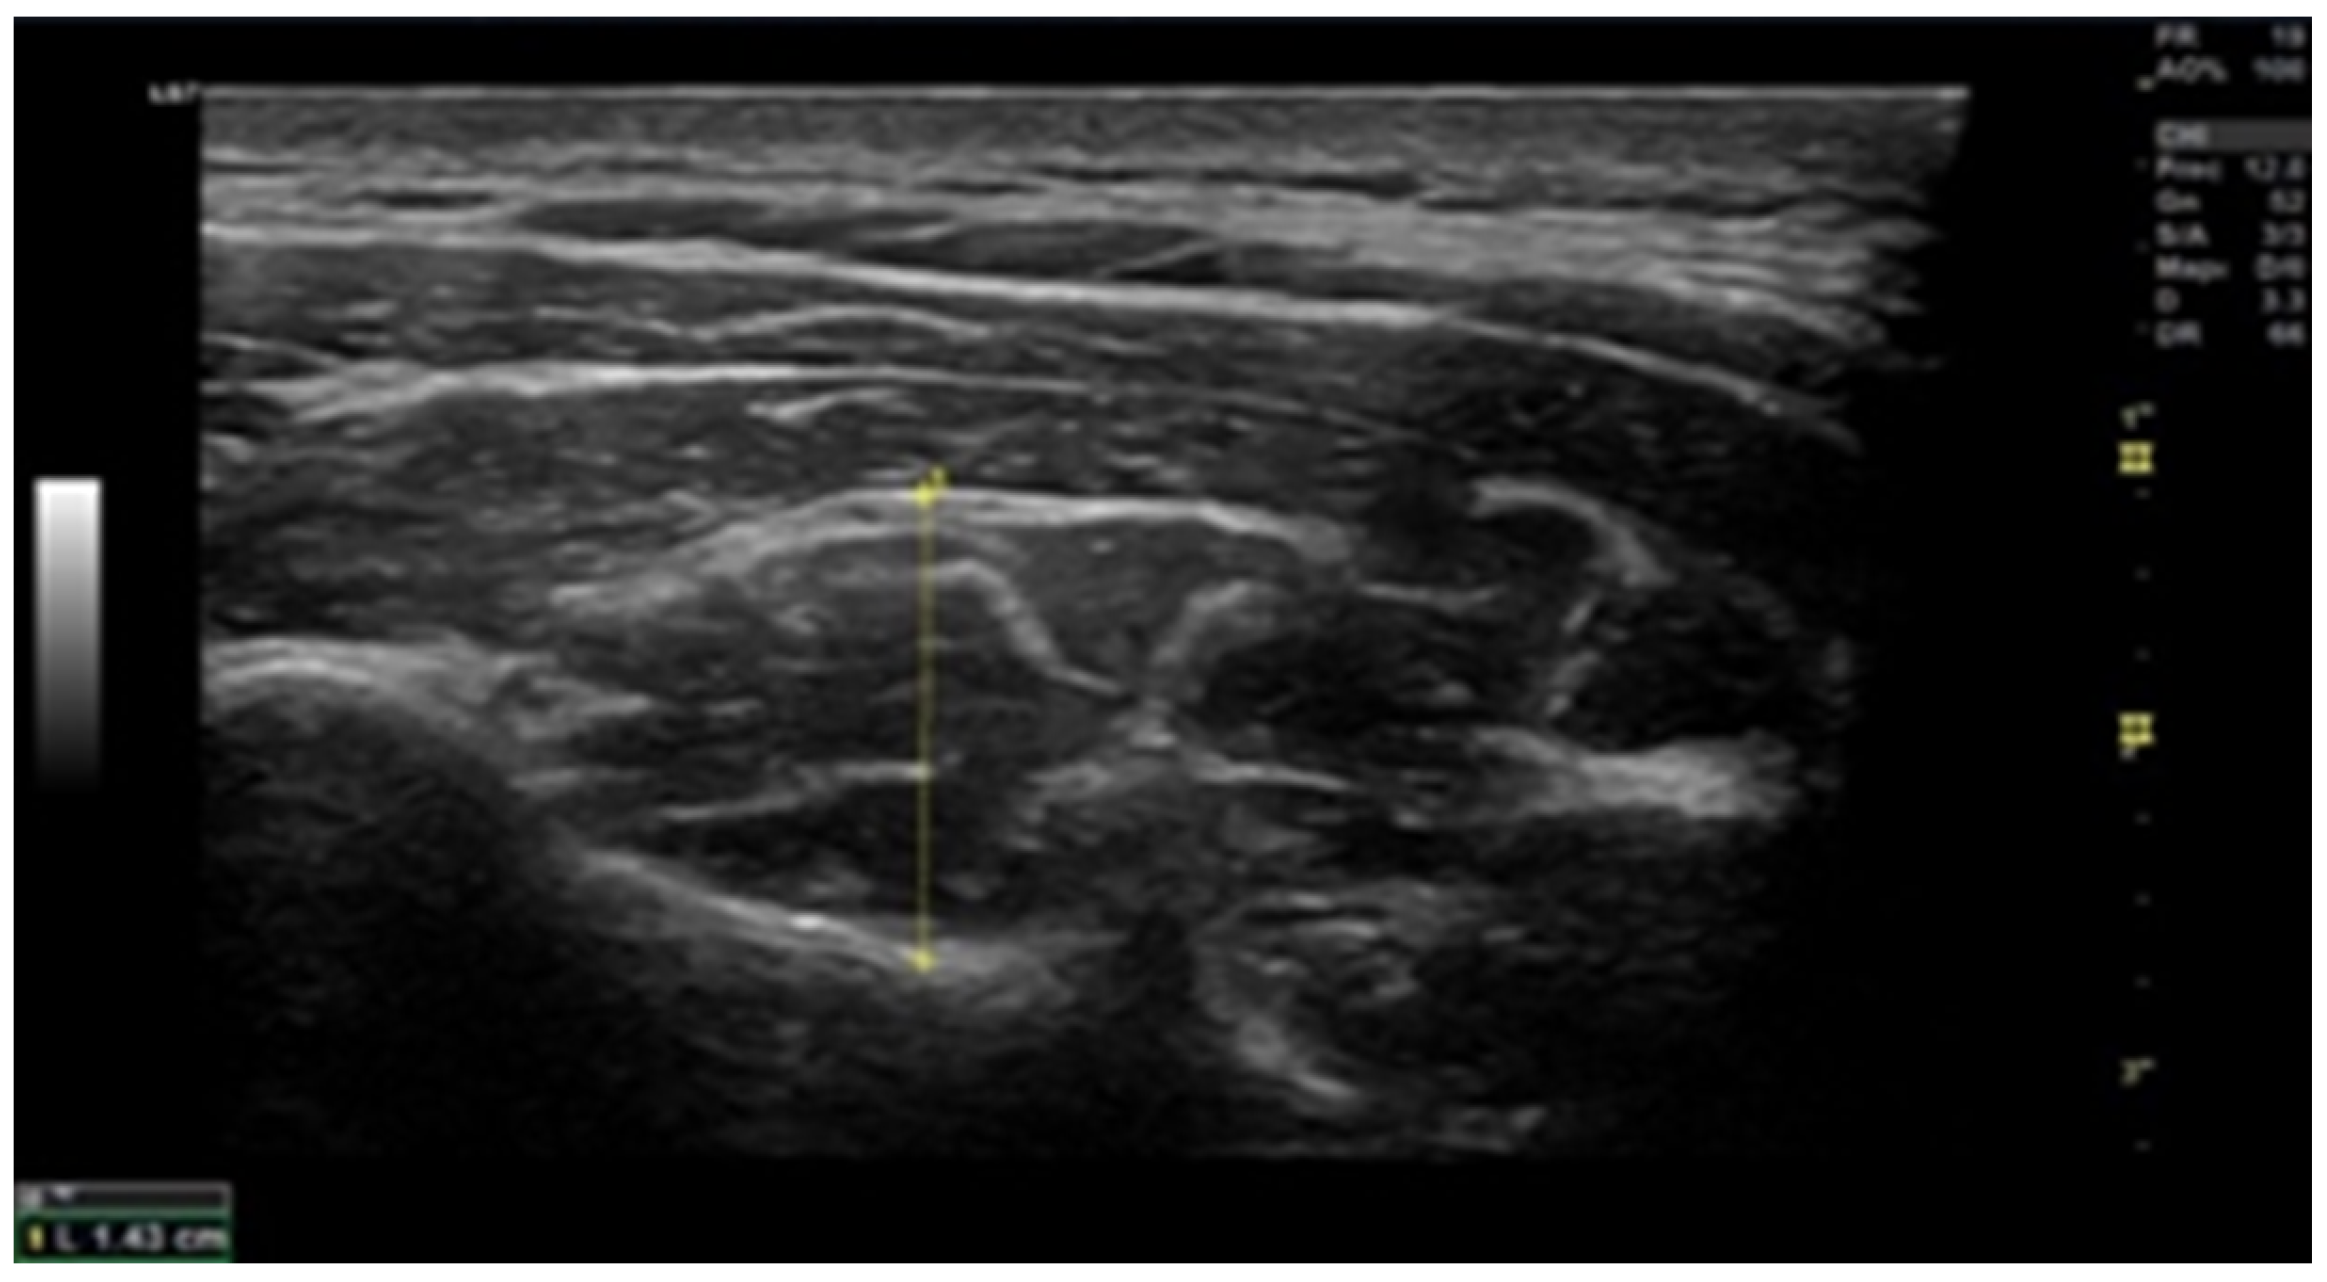

2.6. Muscle Thickness